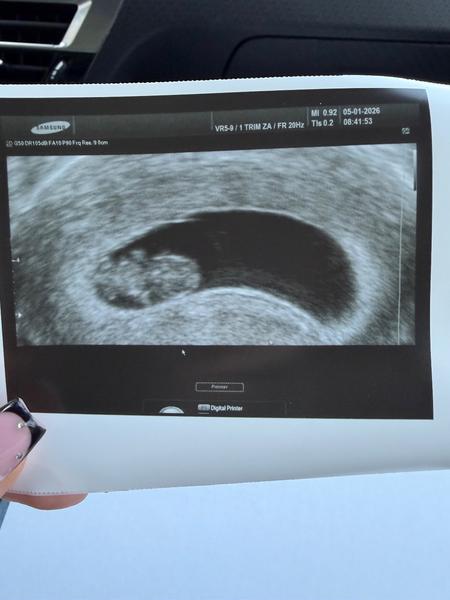

Ahojte baby, ako sa máte? Ja začínam 10tt momentálne😊 posielam fotku sona zo včera